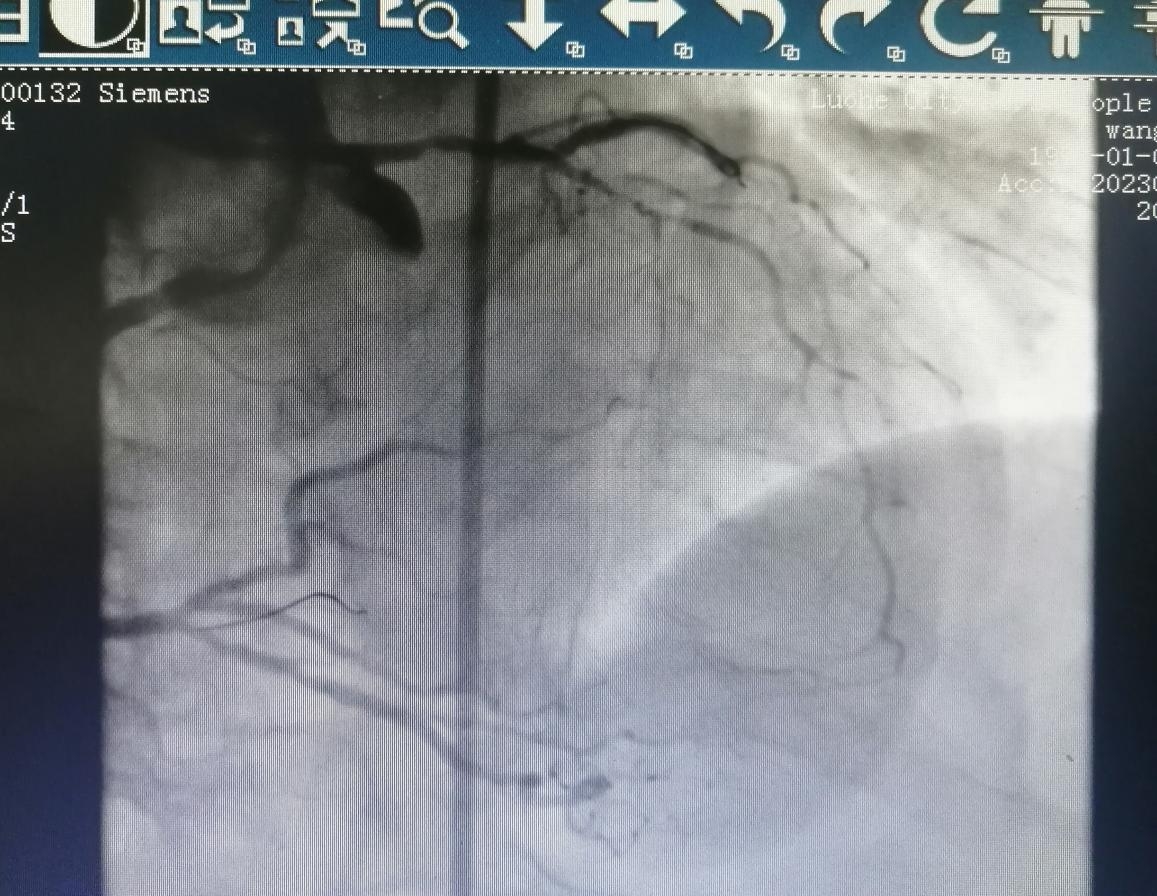

術(shù)前:

術(shù)后:

69歲的王阿姨,患有間斷性心前區(qū)不適2年。近日,因“心前區(qū)不適發(fā)作”入住心血管科。入院后,經(jīng)檢查冠脈造影發(fā)現(xiàn)前降支+回旋支閉塞病變。

金叔宣教授帶領(lǐng)心血管內(nèi)科介入團(tuán)隊(duì)為王阿姨制定了個(gè)體化的手術(shù)治療方案,即行右冠狀動(dòng)脈造影+正向CTO,順利開通閉塞血管。

術(shù)后,王阿姨心前區(qū)不適癥狀較前明顯緩解。